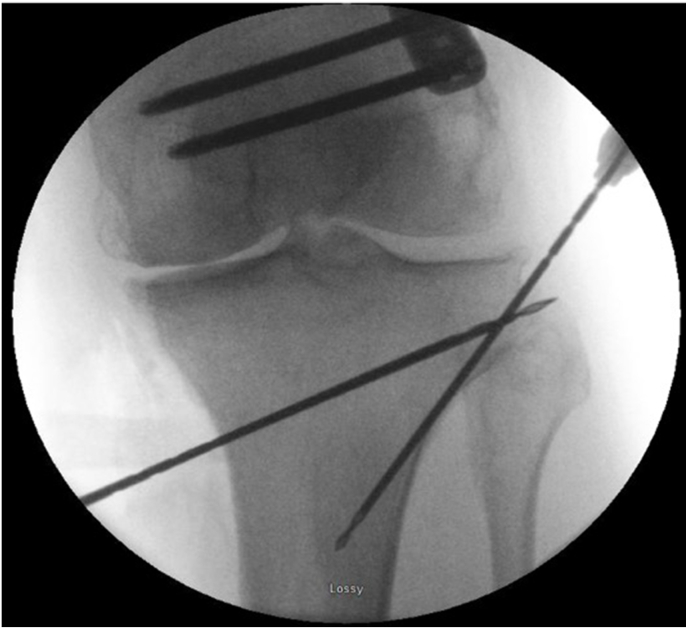

Fig. 5.

A second drill tipped wire, the ‘hinge wire’, is introduced at the hinge through the lateral cortex of the tibia.